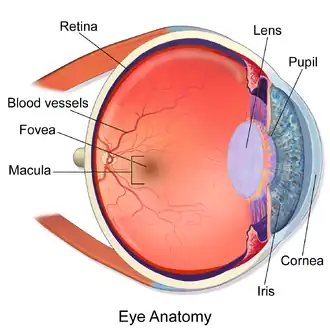

The eye can be considered as a living optical device. It is approximately spherical in shape, with its outer layers, such as the outermost, white part of the eye (the sclera) and one of its inner layers (the pigmented choroid) keeping the eye essentially light tight except on the eye's optic axis. In order, along the optic axis, the optical components consist of a first lens (the cornea—the clear part of the eye) that accounts for most of the optical power of the eye and accomplishes most of the focusing of light from the outside world; then an aperture (the pupil) in a diaphragm (the iris—the coloured part of the eye) that controls the amount of light entering the interior of the eye; then another lens (the crystalline lens) that accomplishes the remaining focusing of light into images; and finally a light-sensitive part of the eye (the retina), where the images fall and are processed. The retina makes a connection to the brain via the optic nerve. The remaining components of the eye keep it in its required shape, nourish and maintain it, and protect it.

The eye is not shaped like a perfect sphere; rather it is a fused two-piece unit, composed of an anterior (front) segment and the posterior (back) segment. The anterior segment is made up of the cornea, iris and lens. The cornea is transparent and more curved and is linked to the larger posterior segment, composed of the vitreous, retina, choroid and the outer white shell called the sclera. The cornea is typically about 11.5 mm (0.45 in) in diameter, and 0.5 mm (500 μm) in thickness near its centre. The posterior chamber constitutes the remaining five-sixths; its diameter is typically about 24 mm (0.94 in). An area termed the limbus connects the cornea and sclera. The iris is the pigmented circular structure concentrically surrounding the centre of the eye, the pupil, which appears to be black. The size of the pupil, which controls the amount of light entering the eye, is adjusted by the iris' dilator and sphincter muscles.

The eye is made up of three coats, or layers, enclosing various anatomical structures. The outermost layer, known as the fibrous tunic, is composed of the cornea and sclera, which provide shape to the eye and support the deeper structures. The middle layer, known as the vascular tunic or uvea, consists of the choroid, ciliary body, pigmented epithelium and iris. The innermost is the retina, which gets its oxygenation from the blood vessels of the choroid (posteriorly) as well as the retinal vessels (anteriorly).

The spaces of the eye are filled with the aqueous humour anteriorly, between the cornea and lens, and the vitreous body, a jelly-like substance, behind the lens, filling the entire posterior cavity. The aqueous humour is a clear watery fluid that is contained in two areas: the anterior chamber between the cornea and the iris, and the posterior chamber between the iris and the lens. The lens is suspended to the ciliary body by the suspensory ligament (zonule of Zinn), made up of hundreds of fine transparent fibers which transmit muscular forces to change the shape of the lens for accommodation (focusing). The vitreous body is a clear substance composed of water and proteins, which give it a jelly-like and sticky composition.[6]